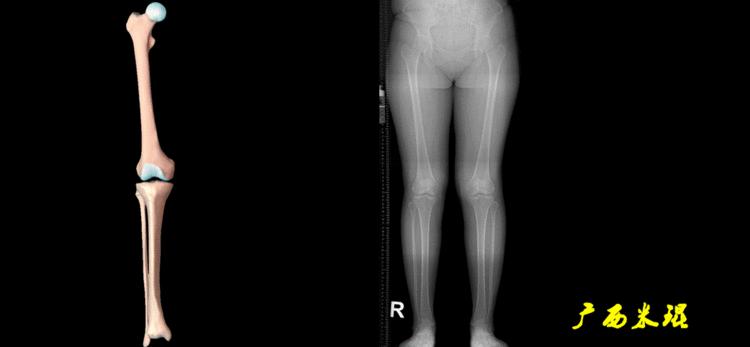

下肢力线及相关角度测量是骨科医生必须要掌握的基础知识,临床上关节疼痛的诊断、截骨矫形和关节置换手术前后等都需要用到这方面的知识,脑海中还没有这方面的概念就去给病人诊断甚至手术治疗,后果是可怕的。刚开始的时候可能感觉这些东西很难,其实只要掌握要点,反复实践,就很快能够熟练的使用它。

下肢力线及相关角度测量的前提是必须拍摄标准的站立位也就是负重位的下肢全长片。目前这样的照片都是放射科的技师在电脑上拼接出来的,大部分医院的DR都能够做到这一点。

无论如何,拍摄出来的下肢全长片必须包含髋关节中心、膝关节中心及踝关节中心,否则对临床是无用的。有了一张下肢的全长照片,我们需要确定下肢关节的中心点,通过中心点画出下肢的各种轴线,然后利用轴线与关节线的相交得出各种所需要的角度。

机械轴要分前后位及侧位,站立前后位(也就是冠状面)股骨头中心与踝关节中心的连线通过膝关节中心,这是下肢的机械轴线,也就是下肢力线,常说Mikulicz线。冠状面的力线评估在临床工作中最常用、最基础、最重要。

站立侧位(矢状面)股骨头中心与踝关节中心的连线也通过膝关节中心,这也是下肢的机械轴线,这也是下肢力线。